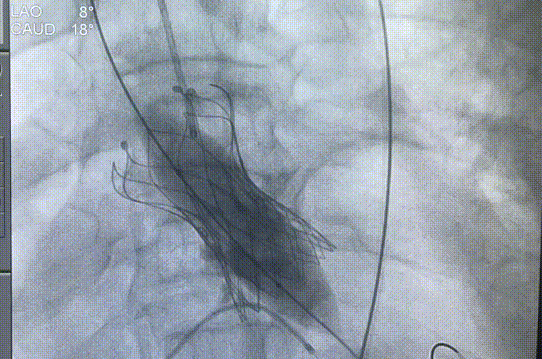

22球囊后扩

后扩后造影

术后主动脉弓部造影,未发现夹层